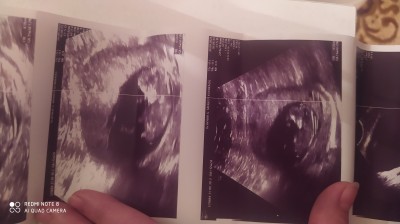

19 Kasım 2022 Hamilelik Dönemi Genel kategorisinde (10 puan) sordu

Cinsiyeti ne sizce söylemedi doktor

Gebelik haftası 12

İçimden kız geçti canım

Kız gibi geldi banada hayırlısı olsun sağlıklı gelsin inşallah

Erkeye benzettim saglikla kucagina alırsın bebisini inşallah canım

Bana kafası büyük geldi oğlumda da buyukdu erkek cocuklarda oyle oluyo diyorlar o yüzden erkek dedim

19 Kasım 2022 (1,304 puan) cevapladı

Resmini de attım